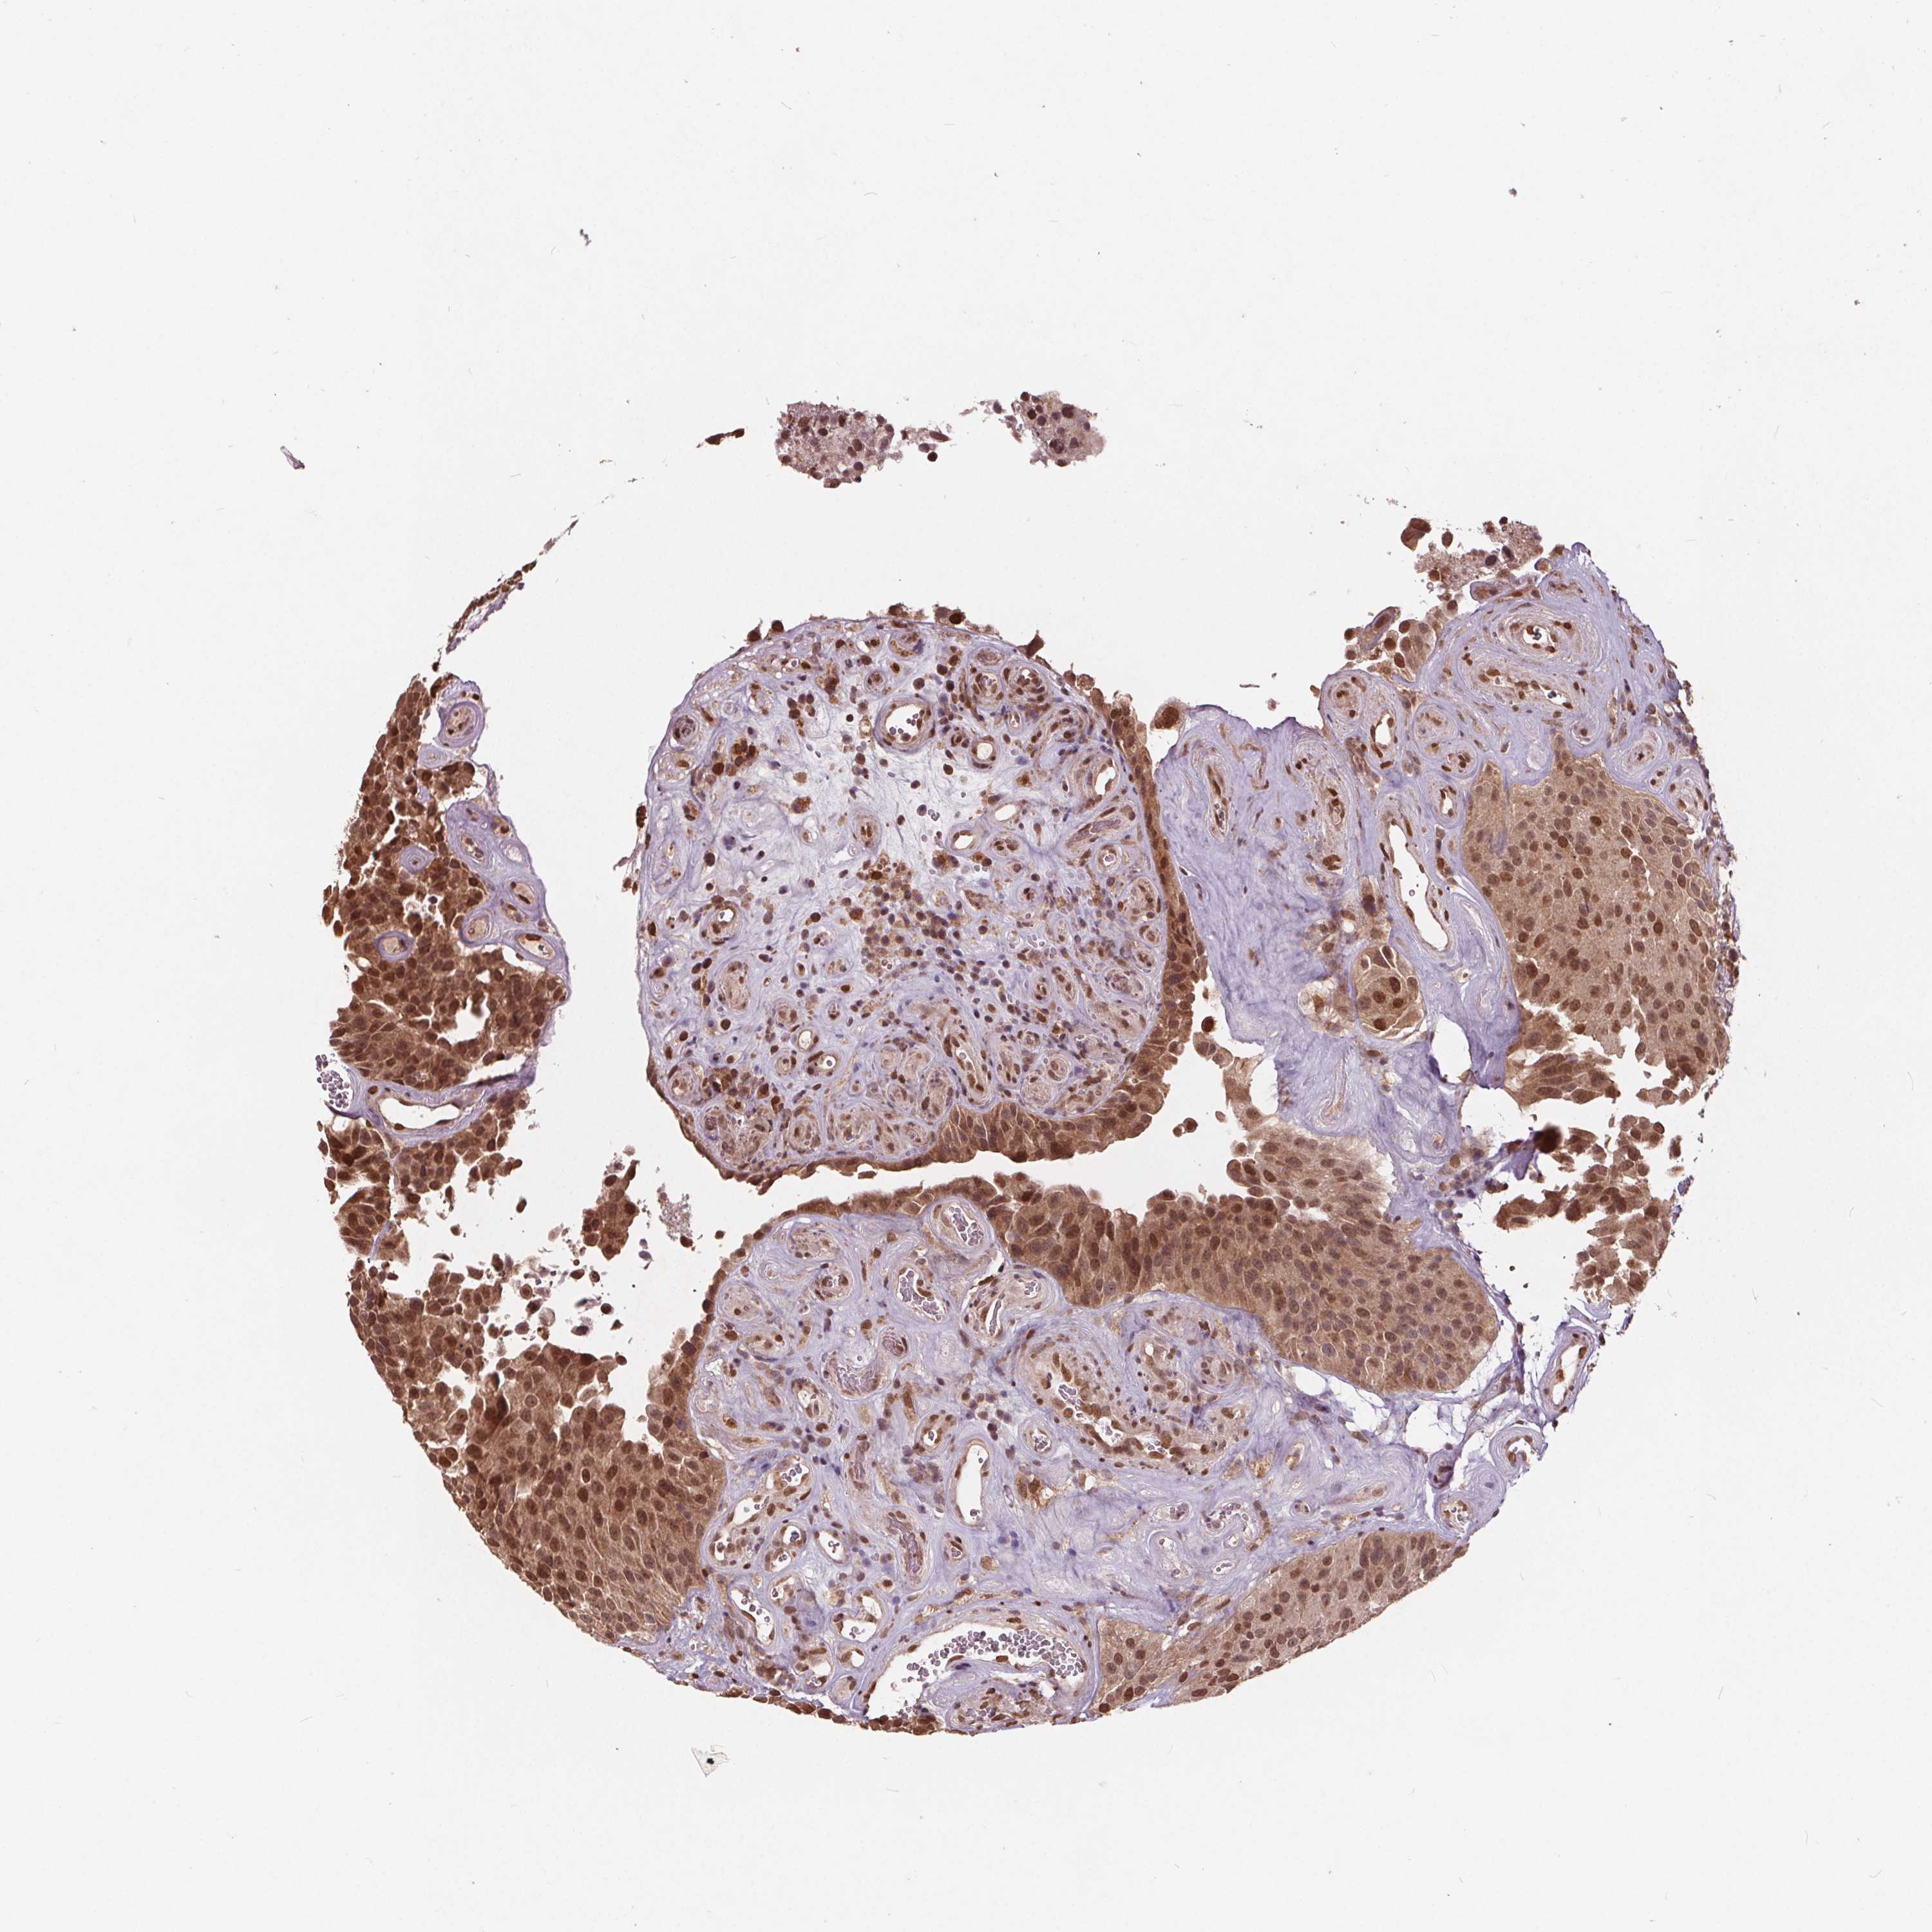

UROTHELIAL CANCER - Protein expressioni

A mouse-over function shows sample information and annotation data. Click on an image to view it in a full screen mode. Samples can be filtered based on level of antibody staining by selecting one or several of the following categories: high, medium, low and not detected. The assay and annotation is described here.

Antibody stainingi

Antibody staining in the annotated cell types in the current human tissue is reported as not detected, low, medium, or high, based on conventional immunohistochemistry profiling in selected tissues. This score is based on the combination of the staining intensity and fraction of stained cells.

Each image is clickable and will lead to virtual microscopy that enables deeper exploration of all samples and also displays staining intensity scores, fraction scores and subcellular localization as well as patient and tissue information for each sample.

Antibody HPA065302

Antibody CAB069903

Staining

High

Medium

Low

Not detected

Intensity

Strong

Moderate

Weak

Negative

Quantity

>75%

75%-25%

<25%

None

Location

Nuclear

Cytoplasmic/membranous

Cytoplasmic/membranous,nuclear

Urothelial carcinoma, High grade

Urothelial carcinoma, Low grade